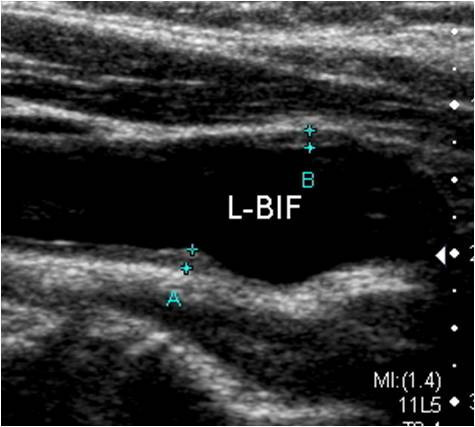

경동맥 초음파(Carotid Ultrasound)는 목 양쪽에 위치한 경동맥(carotid artery)의 혈류 상태를 확인하는 비침습적 영상 진단법입니다. 경동맥은 뇌로 혈액을 공급하는 주요 동맥으로, 이 부위에 죽상경화(동맥경화)가 발생하면 뇌졸중(중풍)이나 일과성 허혈 발작(TIA) 등 치명적인 뇌혈관 질환으로 이어질 수 있습니다.

이 검사는 초음파를 통해 경동맥 내벽의 두께, 혈류 속도, 혈전이나 협착(좁아진 부분) 여부 등을 정밀하게 경동맥 초음파 검사로 알 수 있는 병들을 관찰하여, 뇌졸중 위험성을 사전에 파악할 수 있는 중요한 예방 의료 행위입니다.

5. 혈관 노화 지표

- 내중막 두께(IMT) 측정으로 혈관 노화 정도를 정량화할 수 있습니다.

- 의사가 협착 정도 및 IMT 수치, 혈류 이상 등을 설명